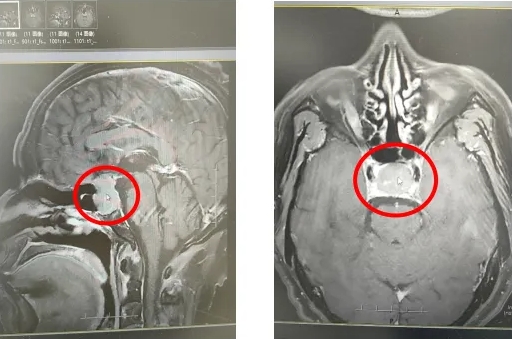

61歲男性患者,以“四肢乏力伴惡心半月余”為主訴入院。患者自訴四肢乏力半月余,伴有惡心于當(dāng)?shù)蒯t(yī)院行頭CT提示顱內(nèi)占位性病變,為求手術(shù)特來我院治療。門診進(jìn)行相關(guān)血液激素等檢查,以“垂體瘤”為診斷將患者收入神經(jīng)外科病房。

入院后,腦外傷腫瘤亞??漆t(yī)療團(tuán)隊(duì)結(jié)合患者的具體臨床表現(xiàn)、影像學(xué)特點(diǎn)、年齡、腫瘤大小、全身健康情況和相關(guān)內(nèi)分泌功能制定出最適合該患者的臨床治療策略。

就該例患者來說,因其蝶竇氣化較好的特點(diǎn),神經(jīng)外科醫(yī)生采取了顯微鏡經(jīng)鼻蝶垂體瘤切除術(shù)。這種手術(shù)方式經(jīng)單側(cè)鼻孔進(jìn)行腫瘤切除,具有損傷小的優(yōu)勢(shì),能夠很好地保護(hù)垂體功能,使得患者術(shù)后恢復(fù)速度較快。